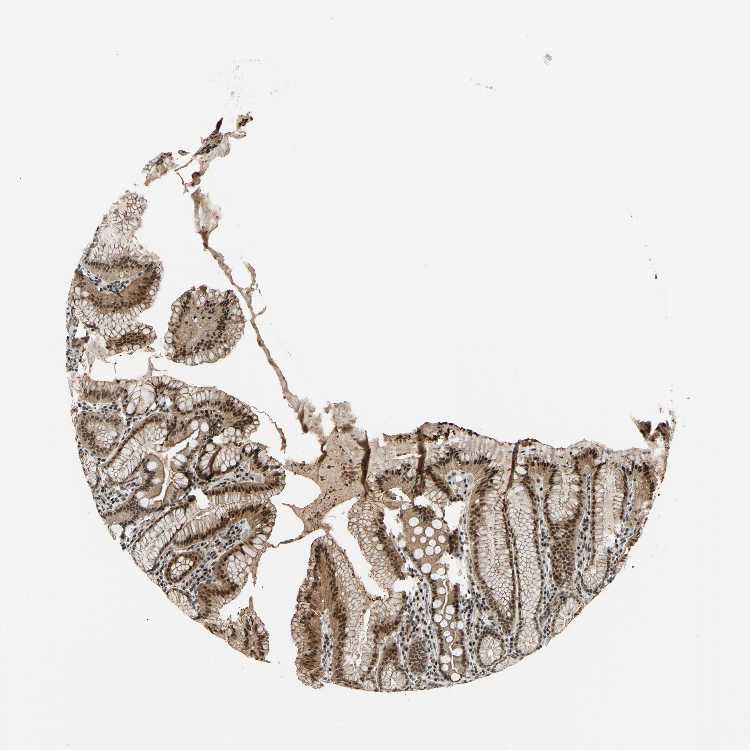

STOMACH 1 - Antibody stainingi

Antibody staining in the annotated cell types in the current human tissue is reported as not detected, low, medium, or high, based on conventional immunohistochemistry profiling in selected tissues. This score is based on the combination of the staining intensity and fraction of stained cells.

Each image is clickable and will lead to virtual microscopy that enables deeper exploration of all samples and also displays staining intensity scores, fraction scores and subcellular localization as well as patient and tissue information for each sample.

Antibody HPA008758

Glandular cells High